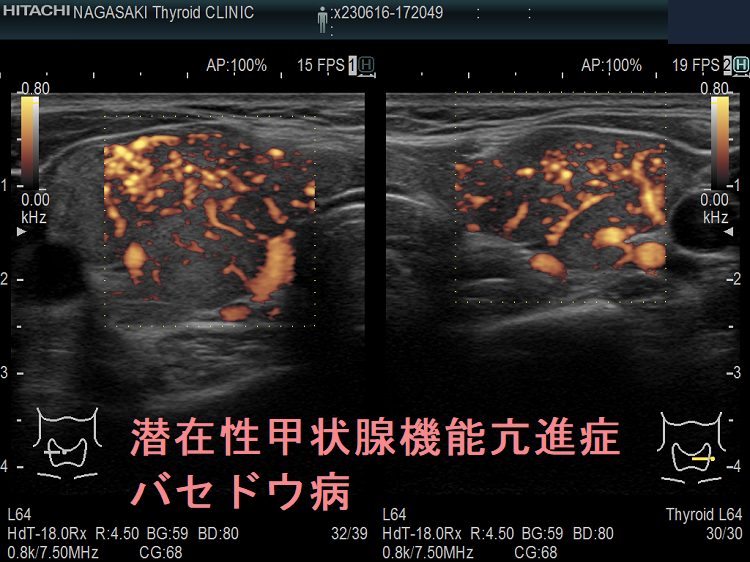

バセドウ病による潜在性甲状腺機能亢進症がある場合は、治療が必要です。医師はおそらく放射性ヨウ素療法またはメチマゾールなどの抗甲状腺薬を処方するでしょう。